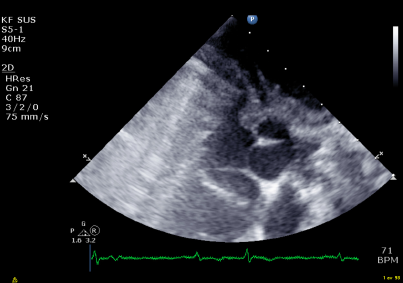

tract (figure 2). The results from the myectomy

could be recorded post-operatively (figure 3).

Figure 3: Shows the results from the Myectomy post-

operatively.